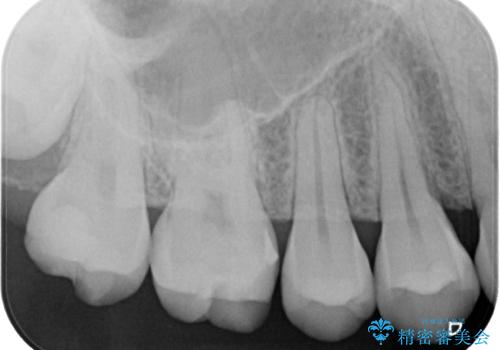

- 銀歯の詰め物が外れてしまったので、これを機にセラミックにやり替えたいと来院されれた患者様です。

虫歯になってしまっているところをしっかりと除去し、形を整えて、精度の高いシリコーンによる型どりを行いました。

また、インレー接着時には唾液や血液による接着力の低下を防ぐためにラバーダム防湿を行っています。